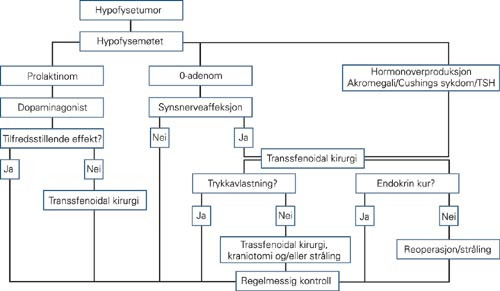

Ved mistanke om svulst i hypofysegropen utføres MR. De fleste adenomer er også synlige på CT, som brukes ved kontraindikasjoner mot MR (pacemaker, magnetiske klips osv.). MR gjøres med 3 mm snittykkelse i sagittal- og koronalplanet før og etter injeksjon av gadoliniumkontrast, ev. supplert med aksiale T1- og T2-vektede bilder (fig 1 – 3). Ved synsaffeksjon skjer utredningen av svulsten i samarbeid mellom endokrinolog (koordinator), nevrokirurg, nevroradiolog, og øyelege. Pasientene drøftes på samarbeidsmøter, såkalte hypofysemøter (fig 4).